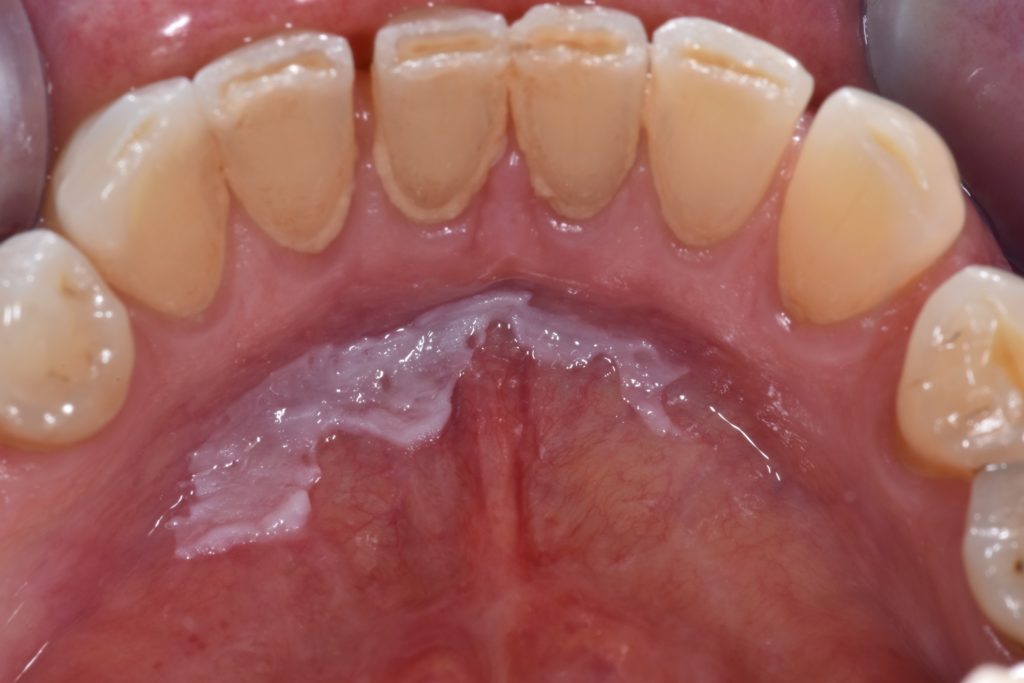

Lesões da mucosa bucal

A mucosa oral fica mais fina, sensível e suscetível a traumas na terceira idade.

Lesões recorrentes podem surgir por próteses desadaptadas, xerostomia, infecções fúngicas e deficiências nutricionais.

A presença de áreas eritematosas persistentes exige atenção, já que alguns quadros podem evoluir para lesões displásicas.

O acompanhamento periódico é essencial para detecção precoce de alterações potencialmente malignas.